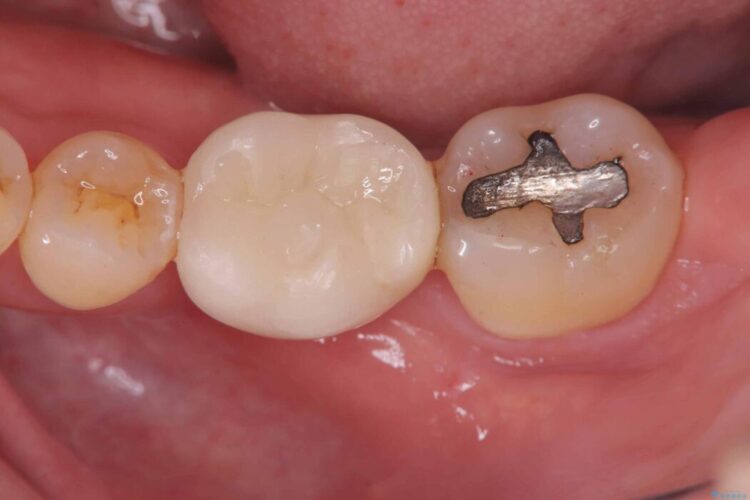

破折したセラミックインレーのやり替え

他院で装着されたセラミックインレー(MOD窩洞)が破折したとご来院されました。

治療期間(治療回数):1ヶ月(2~5回) | 概算治療費:15.4万円(税込)(オールセラミッククラウン14.3万円+仮歯1.1万円)